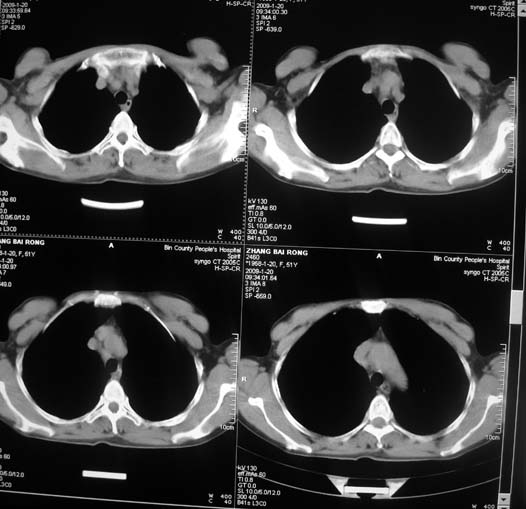

以下是引用zsl6918在2009-1-20 17:30:00的发言:[br]支持右肺下叶背段周围型肺癌,隆突下淋巴结肿大

以下是引用宇宙ct在2009-1-20 16:28:00的发言:[br]周围性肺癌\\纵隔淋巴转移

以下是引用sos.la在2009-1-20 18:01:00的发言:[br]实质性密度均匀肿块.边界清晰,浅分叶.无明显毛刺征,离胸膜近却无胸膜凹陷征,发生在段及段以下支气管,病灶直径远远超过此位置支气管管径而无阻塞征象,7#淋巴结肿大,病理是小细胞未分化癌(局限期)可能性最大.